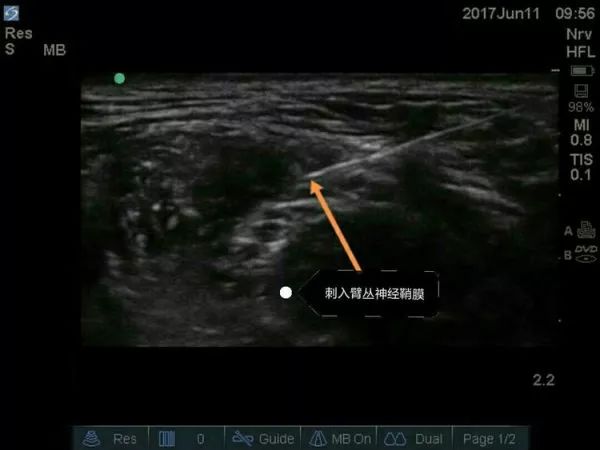

超声引导穿刺针逐渐接触臂丛神经图像

超声引导穿刺针刺入臂丛神经外膜

超声引导下臂丛神经阻滞要点

① 适应证:肩和上臂的手术。

② 探头的位置:横向放置在颈部,横跨颈外静脉表面,约锁骨上3-4cm。

③ 目标:局麻药在前、中斜角肌之间,臂丛的上、中干周围扩散。

④ 局麻药: 15-25ml。

超声下肌间沟水平臂丛的走行图像,上面是胸锁乳突肌,左右是前、中斜角肌。肌间沟水平下可清楚看到呈串珠样的臂丛,C5、C6、C7等。请大家关注下,有的时候能看见5个“串珠”,不要以为是臂丛的5个根即C5、C6、C7、C8、T1,肌间沟往往是在颈椎7水平,怎么可能看到C8、T1,其实就是C5、C6、C7,那为什么是5个“串珠”?因为C6及C7在肌间沟水平已经分出2根,要避免在这2根汇合处之间穿刺而造成C6及C7的神经损伤。